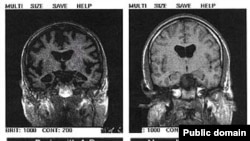

Alzheimerova bolest je najčešći oblik demencije kod starijih osoba i procjenjuje se da od nje u svijetu boluje oko trideset miliona ljudi.